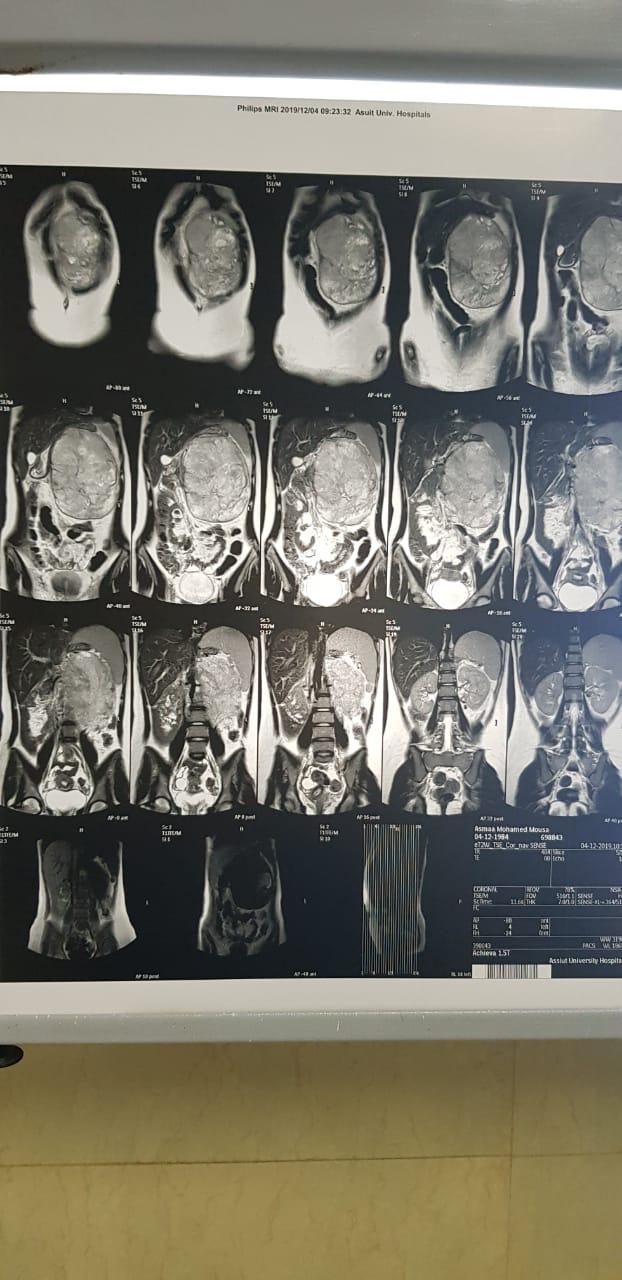

جامعة أسيوط تنجح في إنقاذ حياة طفلة من البحر الأحمر باستئصال ورم ضخم ونادر بالبنكرياس يزن 10كجم

وحول تفاصيل الحالة فقد كشف الدكتور إبراهيم أبو العيون جابر مدرس واستشاري جراحة الأورام بالمعهد وقائد الفريق الطبي المسئول عن العملية أن الطفلة كانت تعانى ألم وانتفاخ بالبطن لمدة عام كامل و فور دخولها إلى المعهد تم إخضاعها لعدد من الفحوصات الطبية وأشعة الرنين والتي بينت وجود ورم بالبطن خلف الغشاء البريتوني يحتل معظم تجويف البطن ليصل إلى ١٥× ٢٠ سنتيمتر ، وباستكشاف البطن تبين وجود الورم في ذيل البنكرياس وهو من الأورام النادرة التي تصيب الأطفال ، وأضاف انه تم بالفعل  استئصال الورم بالكامل والطحال فى عملية جراحية استغرقت ٤ ساعات مع اخذ حد الأمان الواجب للحفاظ علي البنكرياس والمعدة وذلك تم بفضل معاونة الفريق الطبي المسئول عن العملية والذي يضم الدكتور احمد حمدي متميز المدرس المساعد بقسم جراحة الأورام بالمعهد والطبيب محمد خيري والدكتور احمد حسن عثمان الأستاذ بقسم التخدير والإنعاش، وخرجت الطفلة من غرفة العمليات في حالة جيدة ومستقرة .